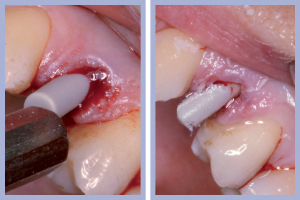

- Figg. 4a, b – Scollamento

- Figg. 5a, b – Estrazione dei canini da latte

- Figg. 6a, b – Estrazione dei canini da latte

- Figg. 7a, b – Toilette chirurgica

- Figg. 8a, b – Mappatura alveolare tramite sonda parodontale

– Estrazione minimamente traumatica degli elementi dentali (Figg. 4-6);

– Sondaggio alveolare e revisione chirurgica (Figg. 7-8);

Dopo l’estrazione, eseguita con i consueti passaggi di scollamento-lussazione-estrazione, la revisione chirurgica tramite cucchiaio alveolare consentiva la completa rimozione dei frustoli di tessuto di granulazione e di legamento parodontale residuo. La preparazione del sito implantare veniva effettuata con approccio flapless, ovvero senza l’esecuzione del lembo.